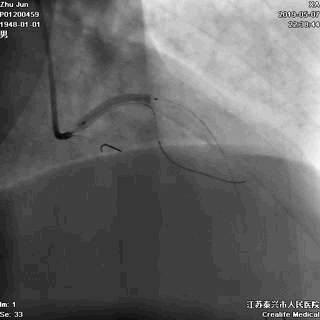

二、导丝到位

---筑牢生命线

导丝分别进回旋支和前降支

LAD和LCX,任一根血管都不能丢!这一步的价值,就相当于是构筑生命线。